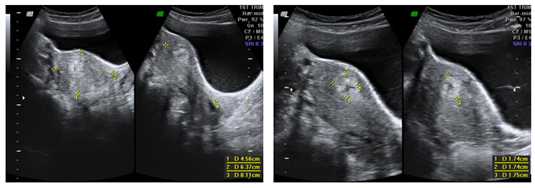

We report a rare case of intramyometrial ectopic pregnancy in a 27year old lady, P3L3 who presented to the emergency department at 8 weeks of gestation with complaints of pelvic pain and haemorrhage not subsiding with medical management. Transvaginal ultrasound revealed an exocentric gestational sac with thick decidua reaction and a “Ring of fire” appearance on color Doppler. Uterine cavity was empty and no adnexal masses visualized. Furthermore, MRI of the pelvis with contrast was done to confirm the location of the ectopic gestation which revealed a well defined T1 isointense T2 hyperintense lesion in the anterior myometrium abutting the junctional zone and showing contrast enhancement. Endometrial stripe was seen separately with an empty uterine cavity. Pouch of Douglas had no free fluid. On diagnostic laparoscopy, an asymmetrically enlarged swollen anterior wall of the uterus was seen. Hysteroscopy was performed concurrently demonstrating an empty uterine cavity. Medical management with methotrexate was initiated following confirmation of the diagnosis. Beta HCG at the time of diagnosis was 9949mIU/ml. She was followed up until the hormone levels returned to baseline and serial scans showed a healed solid collection (Figures 1‒7).

Figure 3 & 4 Transabdominal ultrasound images showing well defined lesion in the anterior myometrium with thick decidual reaction. Endometrial stripe is separately visualized with empty uterine cavity.